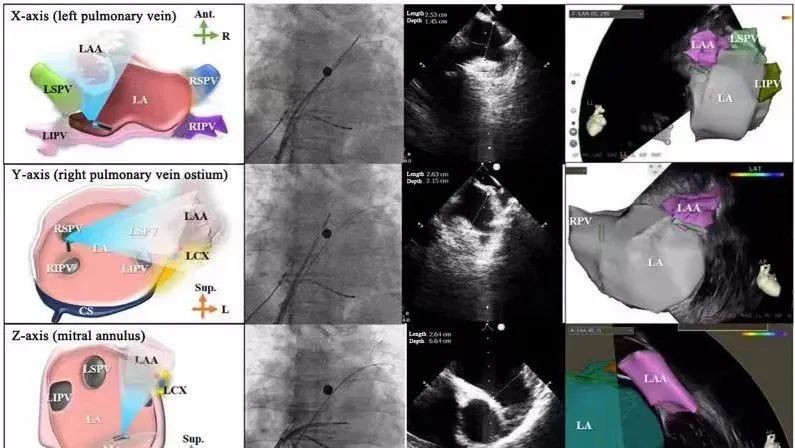

一種與心導(dǎo)管檢查相結(jié)合的超聲心動圖診斷新興技術(shù),通過將超聲探頭置于心腔內(nèi)部,發(fā)射并接收超聲信號,來精確獲取心臟解剖結(jié)構(gòu)、心臟血流動力學(xué)等信息的實時成像。與其他影像技術(shù)相比,ICE技術(shù)具有操作簡單、無輻射、安全性高、手術(shù)效率高、實用等優(yōu)勢,ICE在很大程度上有望取代經(jīng)食道超聲心動圖(TEE),成為電生理和結(jié)構(gòu)性心臟病領(lǐng)域的理想成像方式。

目前ICE技術(shù)已被應(yīng)用于左心耳封堵、房顫射頻消融、二尖瓣成形、房間隔缺損封堵等多種心臟介入手術(shù),應(yīng)用場景主要圍繞心臟電生理、結(jié)構(gòu)性心臟病等領(lǐng)域,目前以電生理應(yīng)用為主。數(shù)據(jù)顯示,我國結(jié)構(gòu)性心臟病介入器械市場規(guī)模已從2017年的4億元增長至2021年的20億元,年復(fù)合增長率達(dá)48.3%;預(yù)計到2025年,該市場規(guī)模將達(dá)到104億元,可以預(yù)見ICE市場規(guī)模也將同步高速增長,未來市場發(fā)展空間廣闊。

心腔內(nèi)超聲(ICE)技術(shù)壁壘極高,國內(nèi)主要廠商核心部件仍舊為進(jìn)口,集成了超聲和圖像處理最前端技術(shù),包括超聲探頭、線纜、軟件成像算法等,是當(dāng)前內(nèi)窺超聲方向最具挑戰(zhàn)的領(lǐng)域。ICE的應(yīng)用經(jīng)歷了2D平面成像、3D三維立體成像、以及4D的實時三維立體成像階段。